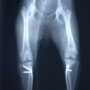

■ 症例24 キャバリア 7か月

左右膝蓋骨内方脱臼(左:グレードⅣ 右:グレードⅢ)

以前から左右後肢の跛行が認められ、整形外科学的検査・レントゲン検査により左右の膝蓋骨脱臼が認められた。症状が重度である左膝の膝蓋骨脱臼整復術を行った。外科手技は縫工筋及び内側広筋の解放、脛骨粗面の外側転位、滑車ブロック形造溝術、内外側関節方の縫縮を実施した。術後一か月時点で、左の膝蓋骨は安定しており経過は良好である。

本症例は成長期における重度の膝蓋骨脱臼であり、術後の再発の可能性もあるため、経過をしっかりと観察していく必要がある。また、今回手術を実施していない右膝に関しても経過を観察し、手術を検討していくこととする。